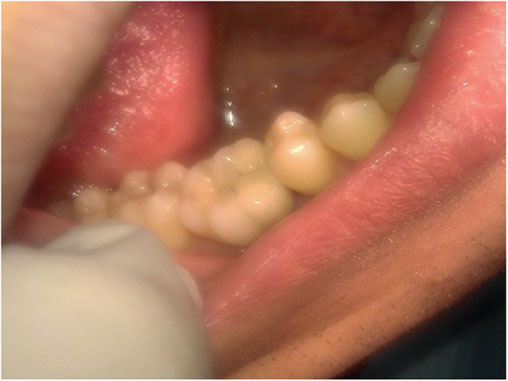

Photo 4. Oral cavity of the same patient: state of alveolar process, dentition and mucous membrane in the area of mandibular dentition defect.